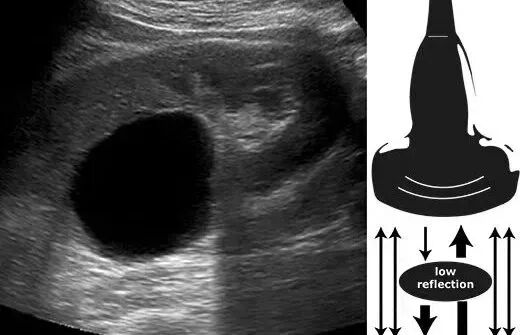

后方回声增强

在超声扫描成像中,当声束通过声衰减很小的器官组织或病变(如胆囊、膀胱、囊肿)时,其后方回声超过同深度的邻近组织的回声。